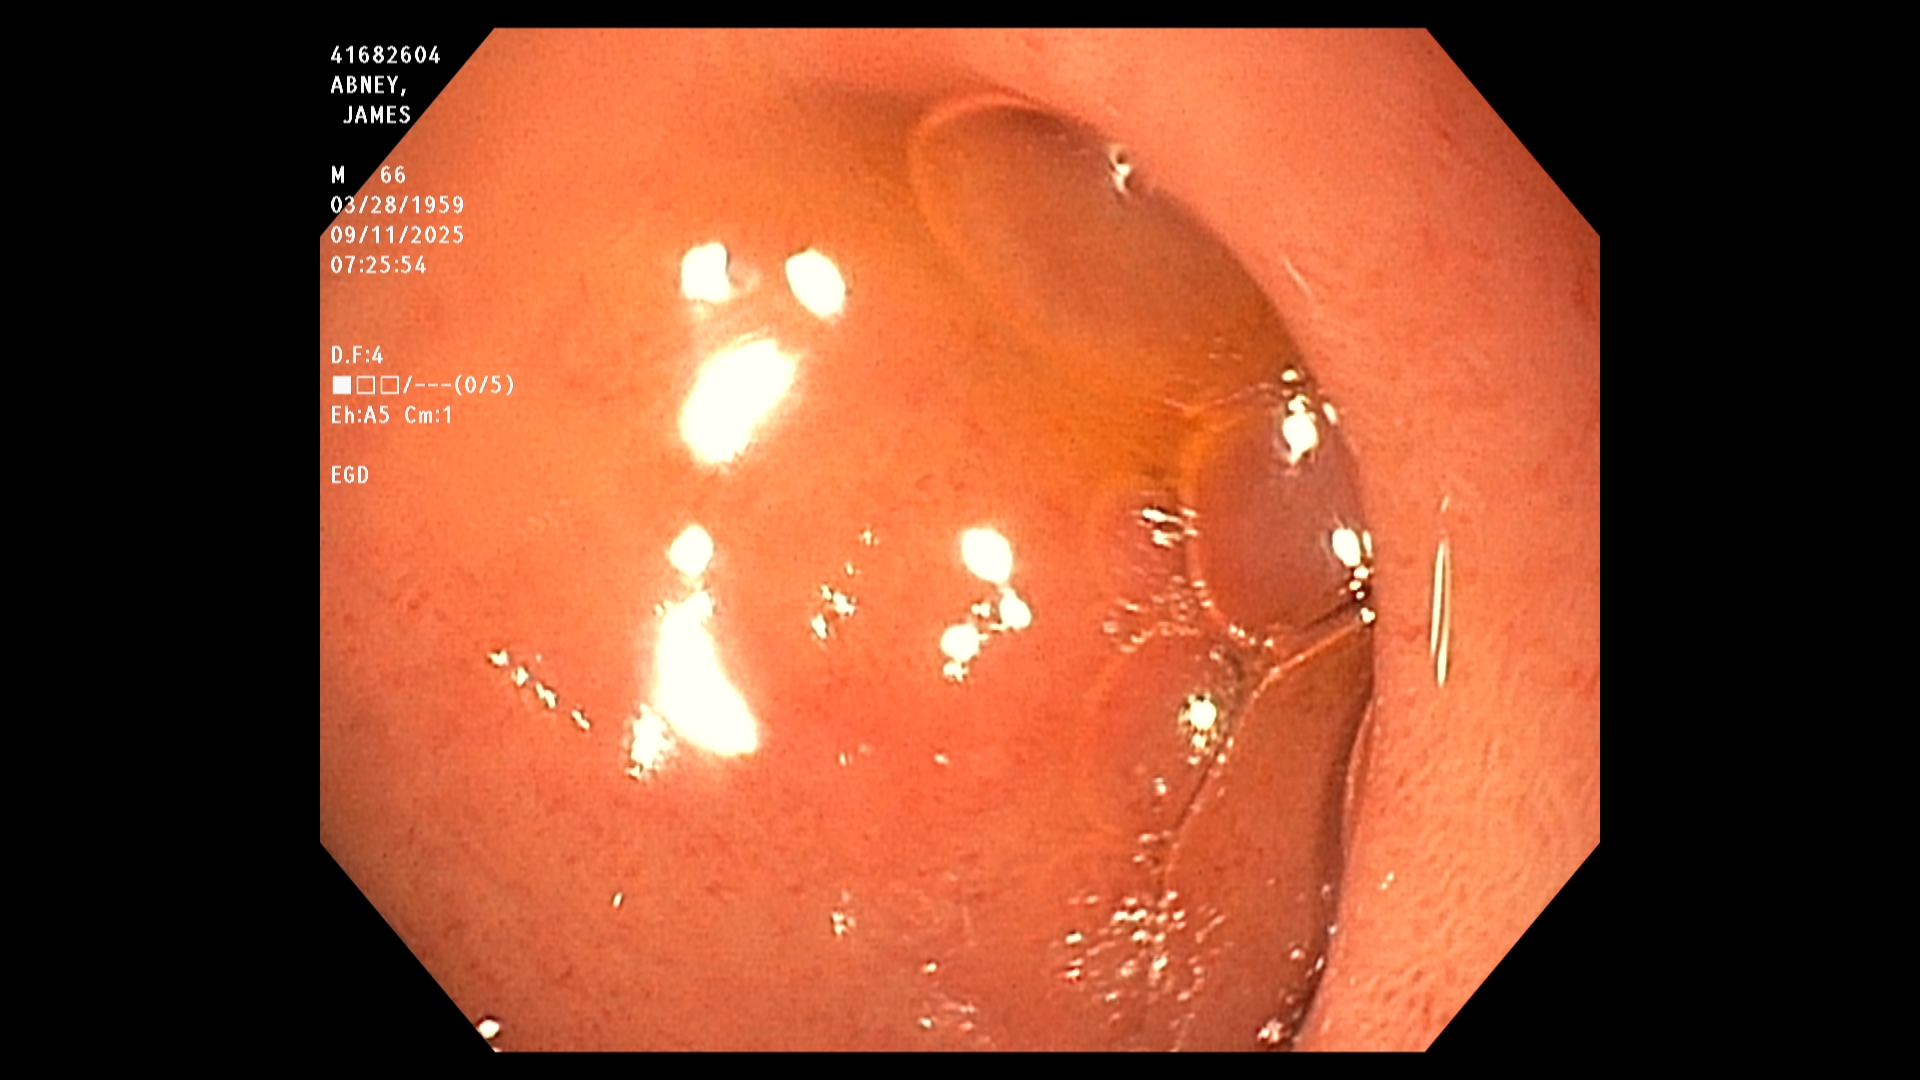

The endoscopist in this study generated a series of images showing the stomach, duodenum,

duodenal bulb, and esophagus, among others. The stomach was imaged first. The image is a

retroflexed view, in which the endoscope was passed through the stomach and the camera

turned backward to take the image, which shows both the stomach and an upstream portion of

the endoscope. The endoscope was next passed into the duodenum, farther down the GI tract,

and then withdrawn while care was taken to observe mucosal detail.

The EGD results in this study were good. In particular, the endoscopist stated that all observed

structures appeared normal and that there was no evidence of any damage, including acid-

reflux damage.